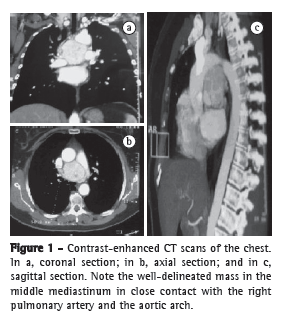

A 60-year-old White female sought treatment in the Thoracic Surgery Department of the Hospital de Clínicas da Universidade Federal do Triângulo Mineiro (Triângulo Mineiro Federal University Hospital de Clínicas) with a 2-year history of moderate, constant pain in the left hemithorax. The patient reported no weight loss and classified herself as a nonsmoker. She had arterial hypertension, fibromyalgia, depression, and Chagas disease, all of which were controlled. Physical examination, laboratory test results, and chest X-ray findings were normal. An echocardiogram showed a solid, heterogeneous opacity between the right pulmonary artery and the aortic arch. Chest CT revealed a well-defined mass in the middle mediastinum, measuring 5.5 × 5.2 × 4.7 cm, which was markedly enhanced after intravenous contrast administration. There were no signs of invasion, although the mass was exerting mild compression on the adjacent vascular structures (Figure 1).